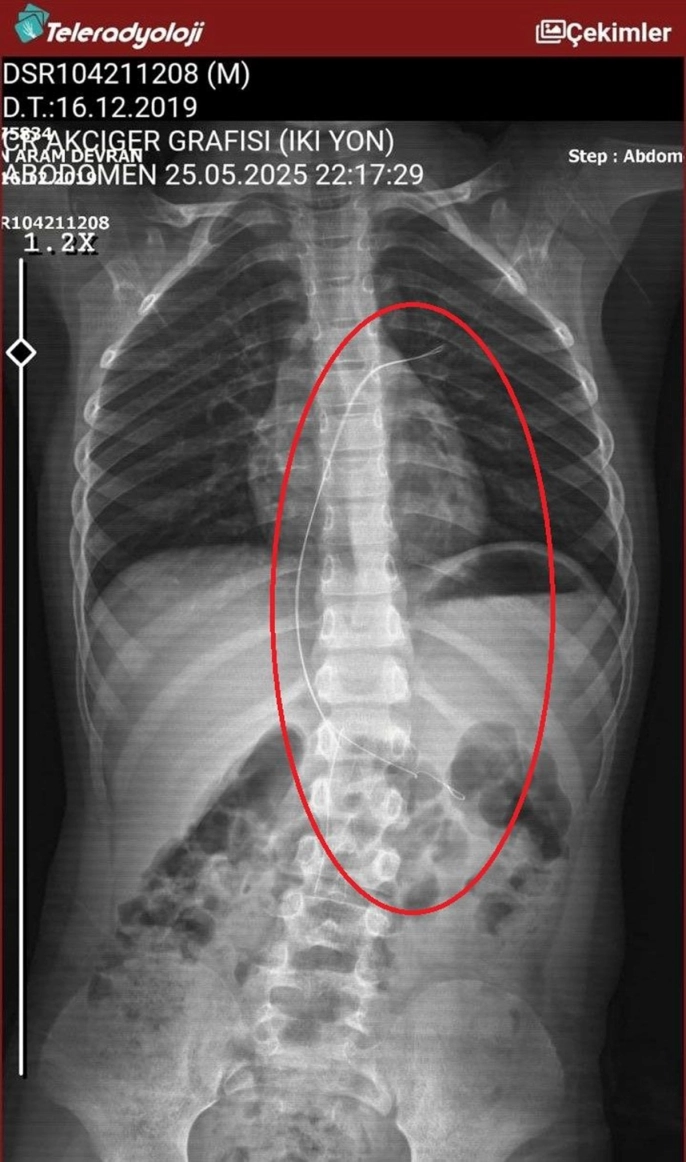

Hastanede çekilen röntgen ve MR görüntülerinde, Aram'ın vücudunda 18 santimetre uzunluğunda bir kateterin bulunduğu görüldü. Diyarbakır'daki Gazi Yaşargil Eğitim ve Araştırma Hastanesi Kadın Doğum ve Çocuk Ek Binası'na sevk edilen Aram, 5,5 saatlik riskli bir ameliyatla bu kateterden kurtarıldı. Ameliyat sonrası yapılan incelemeler, kateterin kalp kapakçığına ve ciğerlerine zarar verdiğini ortaya koydu.